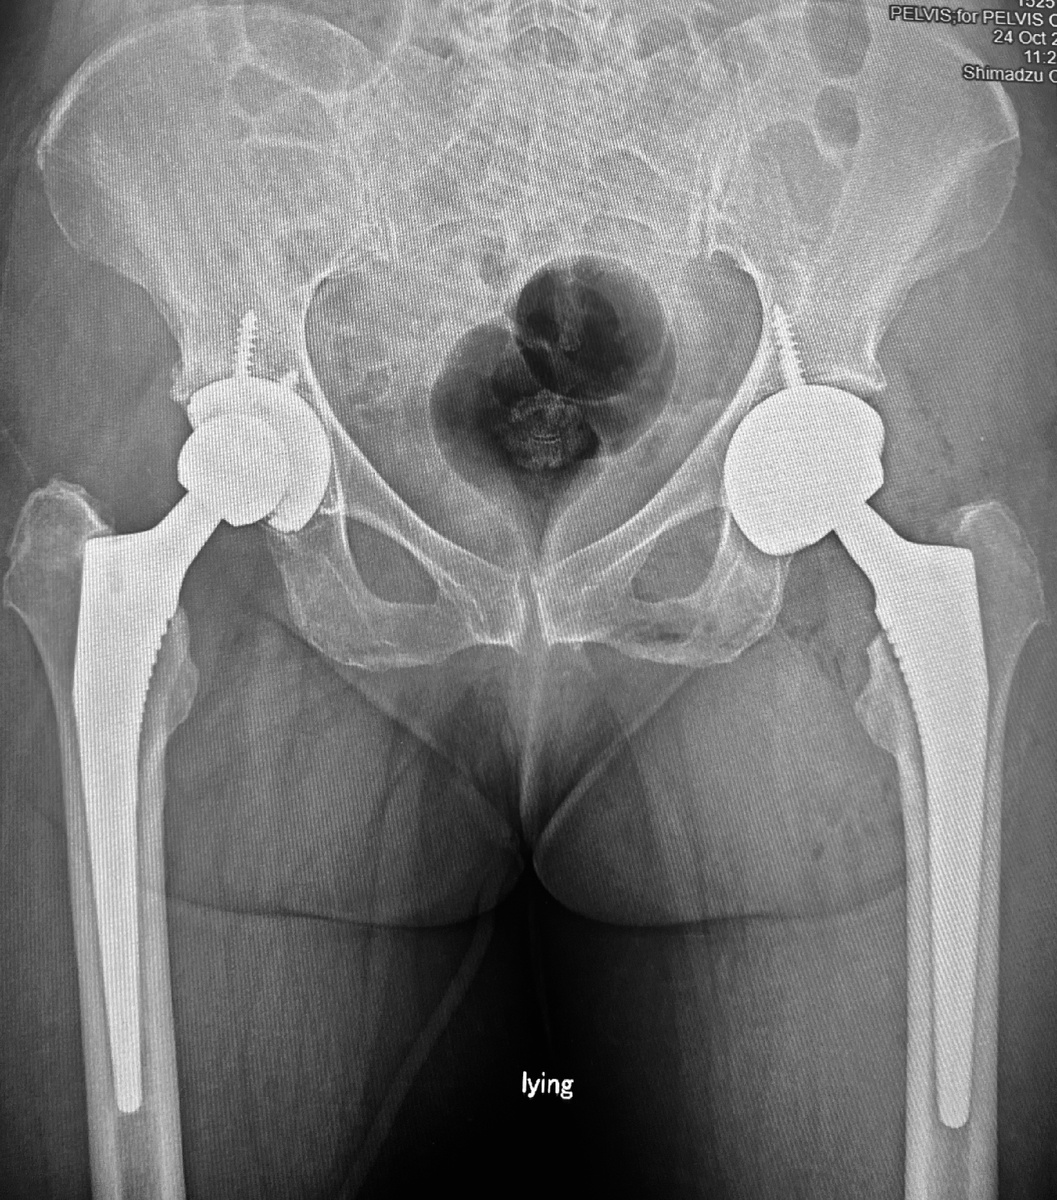

Итак, первая пациентка - 70 с хвостиком лет, после замены второго тазобедренного сустава. Очень спокойная, в меру активная, позитивная, дисциплинированная. И первая операция прошла стандартно, и вторая - без нервов, страхов - на фоне уже имеющихся воспоминаний о том, что это всё не страшно и не больно.

-2

На следующий день после операции встала, через день - пошла по коридору, на третий день лестница и далее - спортзал. Да, у нас есть спортзал, некоторые задерживаются, и занимаются там - не оперированной ногой, а восстановлением походки и т.д. Занимается, но по состоянию уже могла бы быть выписана.

P.S. Да, чуть не забыл: мой ведущий ассистент доктор Коваленко сегодня вернулся из Новосибирска, где в НИИТО произвёл впечатление докладом о нашей пациентке с четырьмя заменёнными суставами. Из инвалида сделали здорового человека )